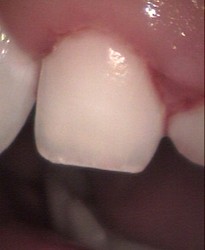

Brown spots on permanent front teeth micro abrasion

direct composite veneers